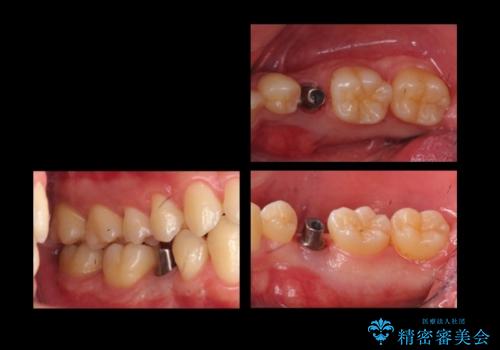

そのため、5番目のインプラントと、7番目の骨整形を同時に行い、整形で取れた7番目の骨をインプラント周囲に移植し、骨を増やすことにしました。

- 42万円 内訳:ストローマンインプラント(1本)20万円、ジルコニアクラウン10万円、シリンダーTeC 2万円 カスタムアバットメント10万円費用は治療当時の料金となります

元々乳歯が残っていた場所であり、骨はたくさんあったため、インプラントを入れるのにそこまで支障はありませんでした。

ただし、奥歯の骨外科治療を同時に行うことで、同時についでに自分の骨を移植できるタイミングだったため行っておきました。